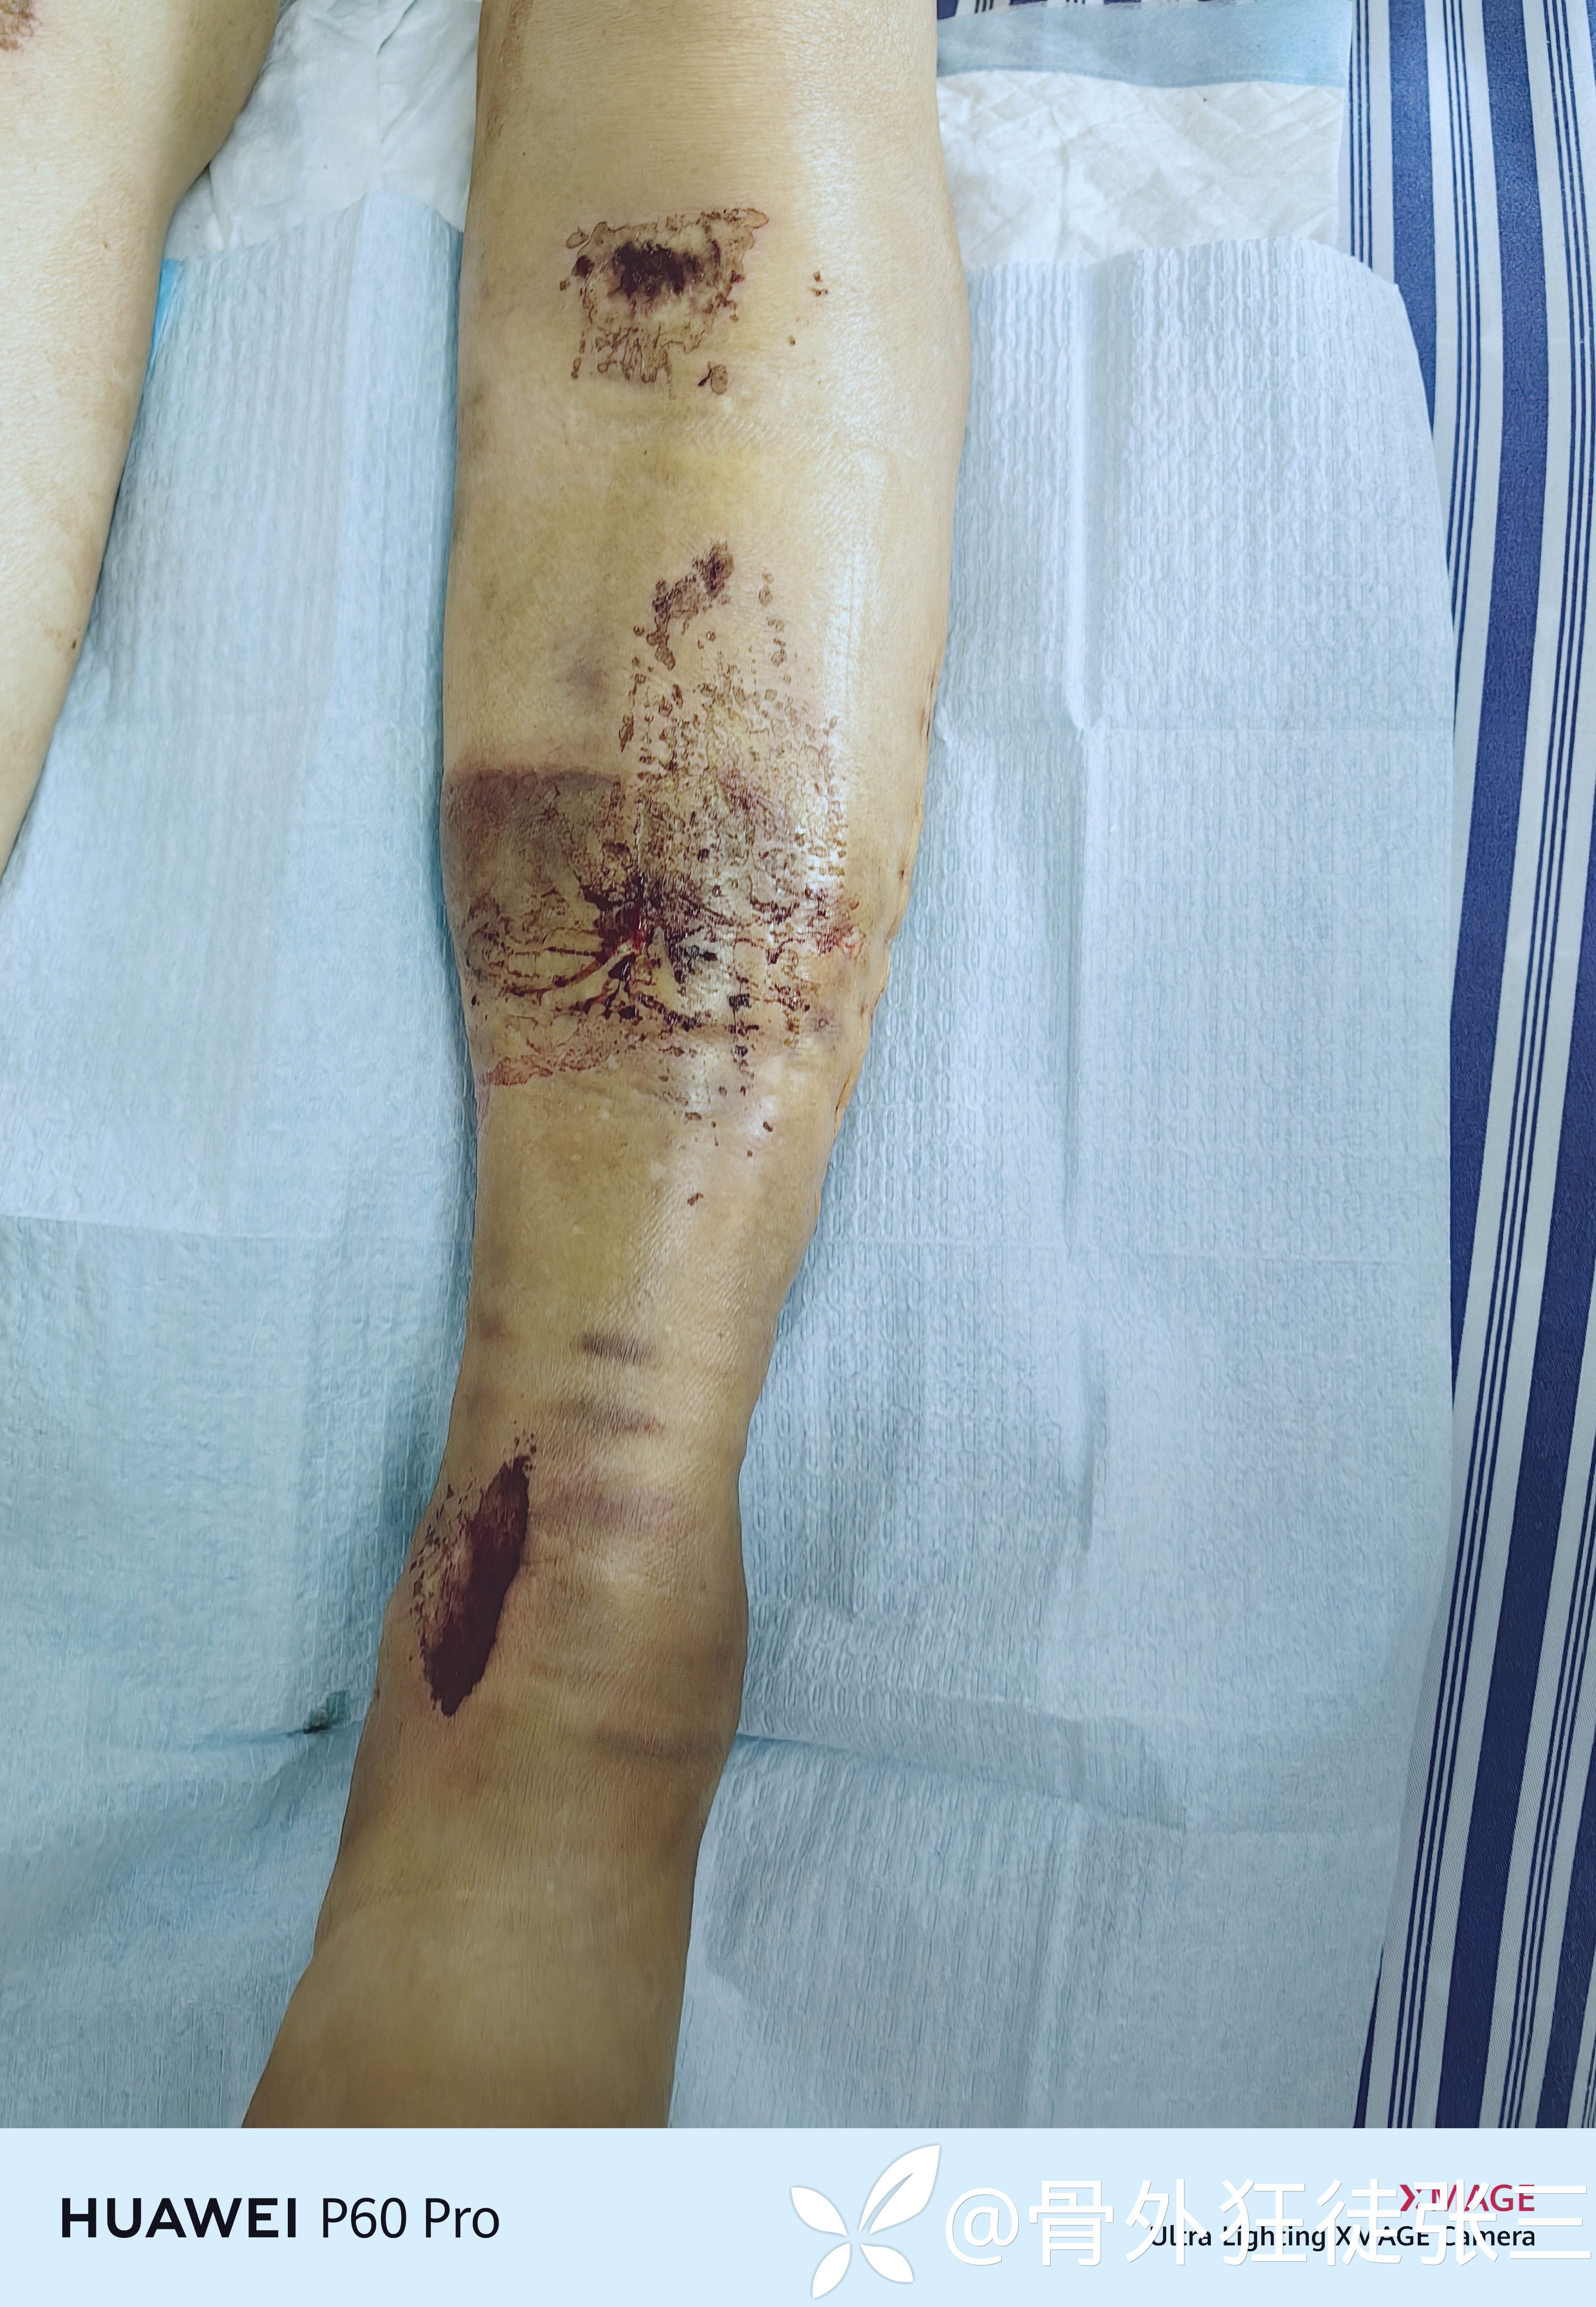

内踝处有一个挫伤创面

腓骨切口,后踝切口

LBD超减张缝合